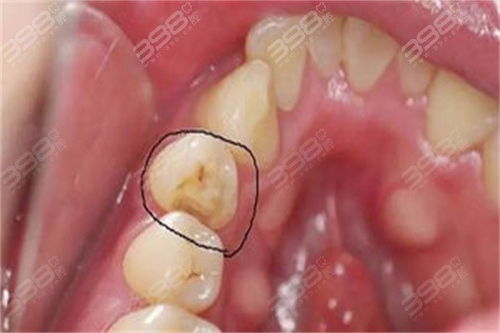

- 龋坏程度与范围: 这是最基本的决定因素,牙齿损坏得越严重,需要填充的材料就越多,去龋坏组织的工作量也越大,自然费用就越高,轻度的浅龋可能只需要小面积充填,而深度龋坏、大面积缺损可能需要更复杂的治疗,甚至可能涉及根管治疗(这时补牙只是后续步骤,费用会完全不同)。